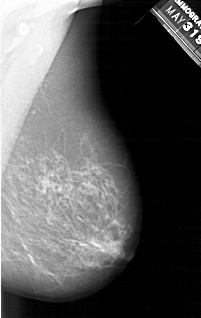

A_1214_1.LEFT_CC